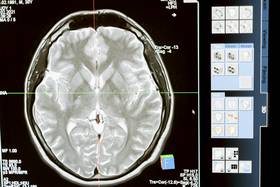

肺癌年輕化!LDCT檢查是什麼?醫生示警「4大族群」最該做造咖更新於 2天前 • 發布於 10月10日13:47「我又不抽菸,怎麼可能得肺癌?」 這句話,其實是醫師最常聽到、卻最想打破的迷思。 根據最新統計,肺癌已連續21年穩坐台灣癌症死因榜首,更驚人的是六成新確診患者根本沒抽過菸。 隨著空氣污染、PM2.5、油煙與基因變異的影響加劇,肺癌早已不再是吸菸族群的專利,而是所有人的潛在風險。 想搶先一步防堵這個「隱形殺手」,醫界公認最有效的工具,就是被稱為肺癌救命神器的「低劑量電腦斷層掃描(LDCT)」。 什麼是「LDCT」?圖片來源:pexels 簡單來說,LDCT是一種輻射劑量更低的胸部X光電腦斷層掃描。 它的輻射量大約只有傳統CT的五分之一,卻能以高解析度影像捕捉到僅0.3公分的微小結節。 也就是說,傳統胸部X光可能要等腫瘤長到2公分才看得出來,而LDCT能在「癌症還在竄芽」時就把它揪出來。 醫師指出,這項技術特別擅長辨識所謂的「毛玻璃樣陰影」,這正是早期肺腺癌常見的影像特徵。更棒的是,LDCT 還能順便偵測到其他肺部異常,如肺纖維化、鈣化斑塊或慢性阻塞性肺病(COPD),一次檢查多重保障。 為什麼要做LDCT?圖片來源:pexels 肺癌可說是少數「越早發現就越能救命」的癌症之一。 根據國健署統計,第0期與第1期的五年存活率高達90%,但若拖到第四期,存活率恐只剩個位數。 更令人心驚的是,多數病患在初期幾乎沒有症狀,沒有咳嗽、沒有胸痛,甚至連喘都不喘。等感覺「哪裡怪怪的」再去看醫生,往往就太晚了。 傳統X光因解析度不夠高,常等到腫瘤轉移才顯影,黃金治療期早已錯過。 LDCT則能提前偵測極小病灶,美國研究更指出,針對重度吸菸族進行LDCT篩檢,能有效降低約 20% 的肺癌死亡率。 台灣自2022年起推動「肺癌早期偵測計畫」,只要符合條件者(例如:重度吸菸者或有家族史)每兩年可免費做一次 LDCT。 誰應該做LDCT?圖片來源:pexels 如果你符合以下任一條件,醫師都建議主動與醫療院所討論是否安排檢查: